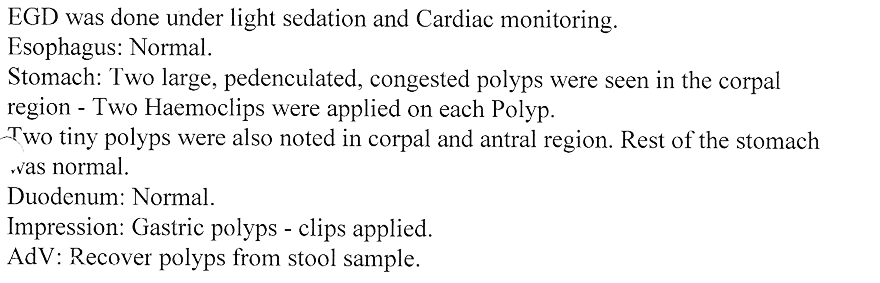

which bleed due to rupture of a blood vessel. Colonic polyps is also an important condition to diagnose because

polyps have potential of becoming cancerous in future. Removal of polyp by polypectomy without

open surgery can offer cure in the early stage of cancer. A proper follow-up can keep the patient free from cancer.